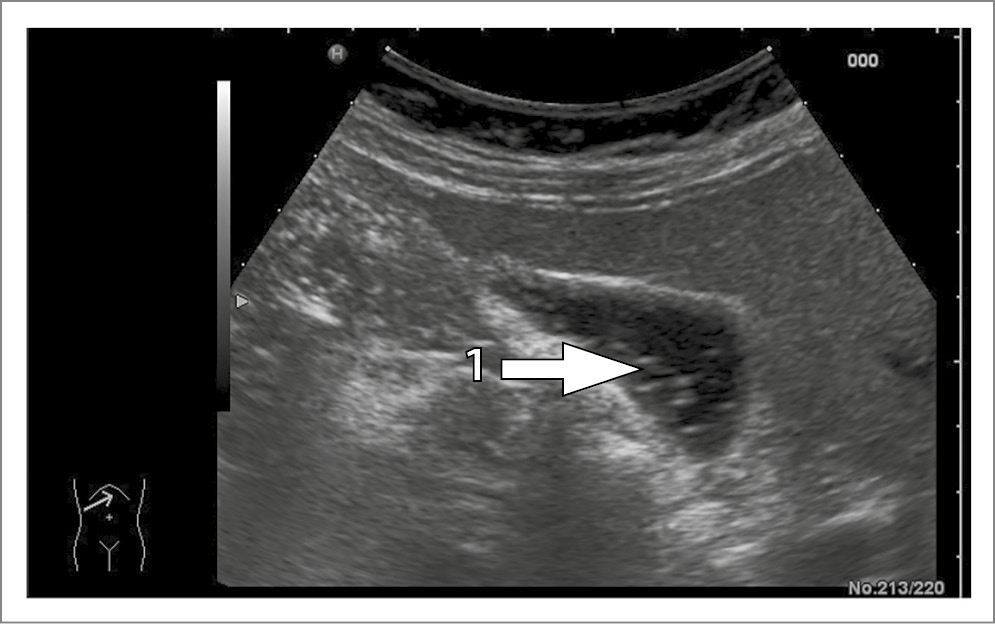

Актуальность ЖКБ в структуре заболеваний гастроэнтерологического профиля подчеркивается не только широким распространением данного заболевания, достигающим 20% в мировой взрослой популяции, но и риском осложненного течения, требующего оперативного вмешательства [2, 3]. БС, входящий в континуум ЖКБ, рассматривается как ступень, предшествующая формированию холестериновых камней, успешно поддающаяся лекарственной терапии [7, 19]. Основным методом диагностики БС является трансабдоминальное ультразвуковое исследование, позволяющее дифференцировать тип сладж- синдрома. Так, 1-й тип представляет собой взвесь маленьких, точечных и смещаемых гиперэхогенных частиц без акустической тени, выявляемых при изменении положения тела пациента (рис. 4).

Рис. 4. Билиарный сладж 1-го типа: 1 – гиперэхогенные включения в полости желчного пузыря.